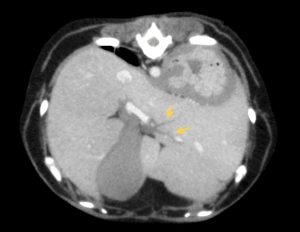

頻回の嘔吐と食欲不振を訴えて病院に来られたワンちゃん、血液検査で肝酵素と炎症マーカーの重度上昇があり、以前から胆嚢粘液嚢腫を抱えていたため、破裂などを疑わせる状況でした。超音波検査とCT検査では、胆嚢周囲の炎症、総胆管と肝内胆管の肥厚が見られましたが、破裂や閉塞所見は認めませんでした。胆嚢破裂や閉塞がない状態で、このような劇的な症状が起きることは比較的珍しいと思います。しかし、胆嚢粘液嚢腫が病態に関与していることは間違いなかったため、飼い主様に同意してもらい、その日のうちに胆嚢摘出術を行いました。

↑総胆管壁の肥厚

↑肝管の肥厚

↑胆嚢周囲(鎌状間膜)の炎症所見